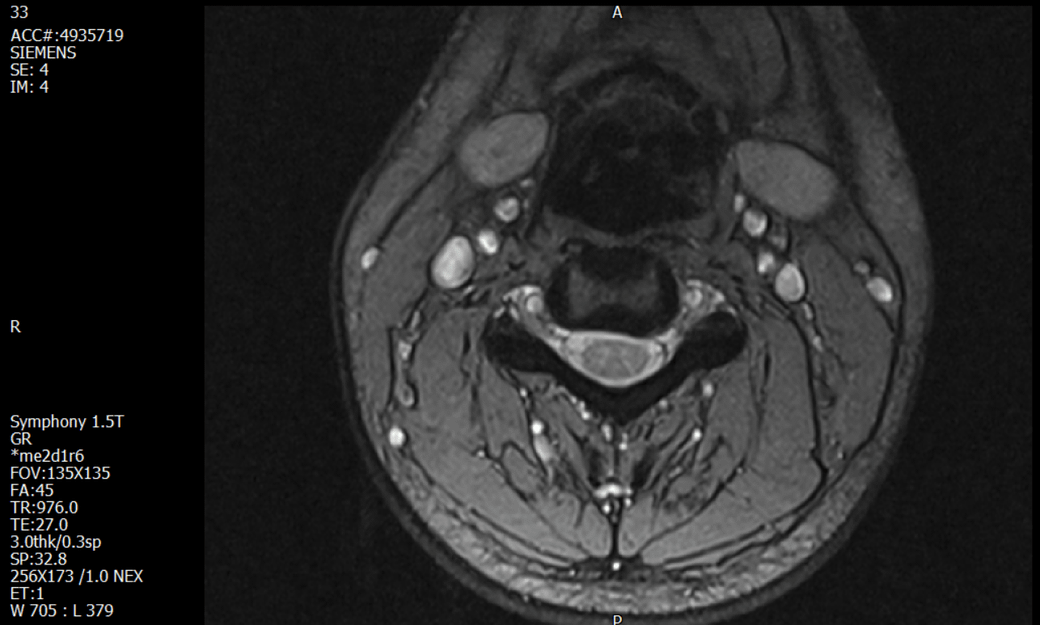

경추 요추 디스크 MRI판독 부탁드립니다.

- 3개월전 좌측 상지 저림(힘빠짐) 발생. 이틀뒤 에 좌측 하지 저림(힘빠짐) 발생.

(힘이 축처지는 느낌이라서 힘빠짐이라고 하지만, 실제 근력 문제, 감각이상, 활동 문제 없음)

-11월, 증상발생 직후 잠실소재 척추전문병원 MRI 요추경추 촬영 후 신경외과 박사 진료, 허리는 매우 건강, 경추는 퇴행성 진행되고 있지만 디스크라고 보기 어려움. 신경막만 살짝 건드리는 정도고 이 정도로 힘빠짐이나 저림이 오지 않고 원인은 다른 곳에 있을 가능성.

-12월, 분당서울대병원 재활의학과 진료, MRI 영상보고 딱히 다른 말은 없었음. 근전도 검사해보자 해서 신경전도, 근전도 검사 진행, 검사결과 이상없었고, 신경쪽 문제는 아예 배제해도 될것이라고 함. 정신쪽에 기인한 문제일 가능성 제시.

-올해 1월, 국립암센터 재활의학과 진료, 병명을 찾기가 쉽지 않을 것

-올해 1월, 분당서울대병원 신경과 진료, MRI영상보더니 디스크가 있고 저림과 힘빠짐이 이에 기인했을 가능성이 충분히 있다고함. (경추만 말한것인지 요추도 포함인지 모르겠으나 디스크 시술 방안을 제시함) , 팔다리가 우연이 동시에 저림이 올수 있는지에 대해서 물었더니 이틀 상간으로 발생했기 때문에 동시라고 보기 어렵다고함...

1. MRI 상 , 경추와 요추에 디스크가 있나요? 있다면 좌측 팔과 다리에 저림 및 힘빠짐을 줄 정도인가요?

2. 혹시 영상의 퀄리티가 떨어져서 의사끼리 의견이 다른것일까요? MRI는 1.5T로 촬영된 것인데, 3.0T로 재촬영할 필요가 있을까요?

3. 디스크로 인한 증상이라면, 목과 허리의 디스크가 이틀 상간으로 문제가 생길수 있나요?

특히나 요추MRI는 문제가 없다고 들었던 터라 다리저림은 어떻게 설명할수있는것인지 모르겠네요.

• 1. MRI 사진을 보았을 때 디스크를 의심해볼 수 있는 소견이 살짝살짝 보이긴 합니다만, 상하지의 저림 및 힘빠짐을 유발할 정도인지는 솔직히 회의적입니다.

2. 영상의 퀄리티는 나쁘지 않아 보입니다. 굳이 재촬영을 하실 필요는 없어 보입니다.

3. 개인적으로는 디스크로 인한 증상이 아닐 것으로 보나, 만약 디스크가 맞다면 우연하게 목과 허리 디스크 발병이 이틀 간격을 두고 나타났을 가능성을 생각해야 하는데, 현실적으로 그 가능성이 높지 않습니다.

4. 말씀하신 것처럼 특히 요추부 MRI는 디스크를 찾기 어렵습니다.

상기 MRI 소견으로는 심한 증상을 보일 정도는 아니며 디스크의 가능성은 적어보입니다.